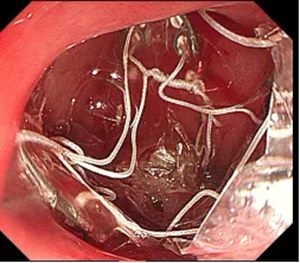

▲ 支架释放在肠道